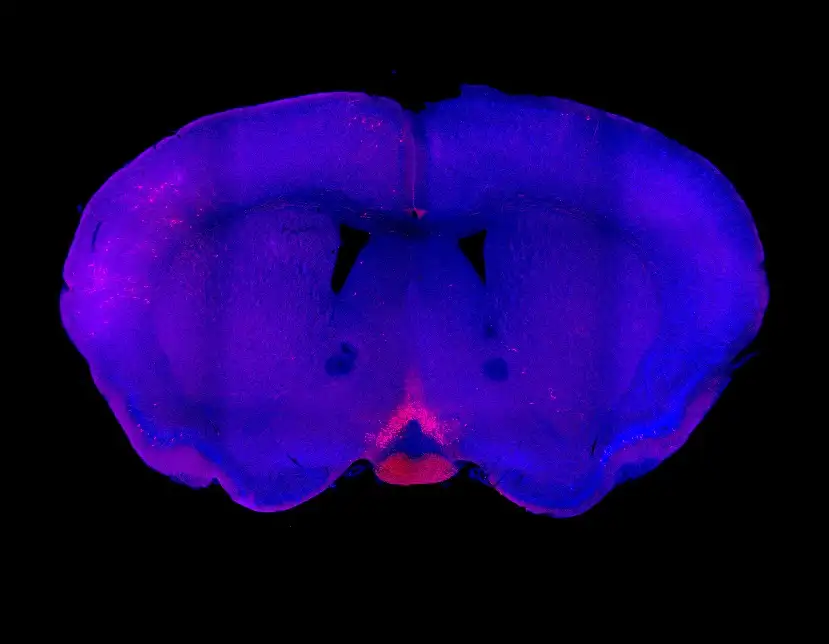

A multi-institutional team of scientists led by Richard Lang, PhD, from Cincinnati Children’s reports in the journal Nature has located, in mice, certain neurons inside the brain that express the protein Opsin 5, which can detect a specific wavelength of violet light from the sun. Those neurons, in turn, send signals that influence a number of body functions—including metabolism.

| Original title: | A neuropsin (Opsin 5) deep brain photoreceptor mediates violet-light suppression of thermogenesis |